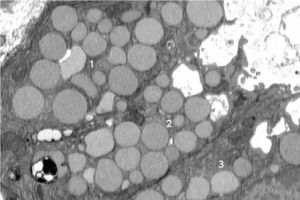

یک مطالعه جدید نشان میدهد که سلولها برای التیام و جوان شدن دوباره، مواد زائد درون خود را استفراغ میکنند. محققان یک فرآیند سلولی احیاکننده جدید به نام کاتارتوسیتوز(cathartocytosis) را شناسایی کردند که در آن سلولها برای التیام خود «استفراغ» میکنند. به نقل از آیای، محققان یک فرآیند سلولی جدید را شناسایی کردهاند که با تبدیل شدن به سلولهای بنیادی به سلولهای آسیبدیده کمک میکند تا التیام یابند.

محققان یک فرآیند سلولی احیاکننده جدید به نام کاتارتوسیتوز(cathartocytosis) را شناسایی کردند که در آن سلولها برای التیام خود «استفراغ» میکنند.